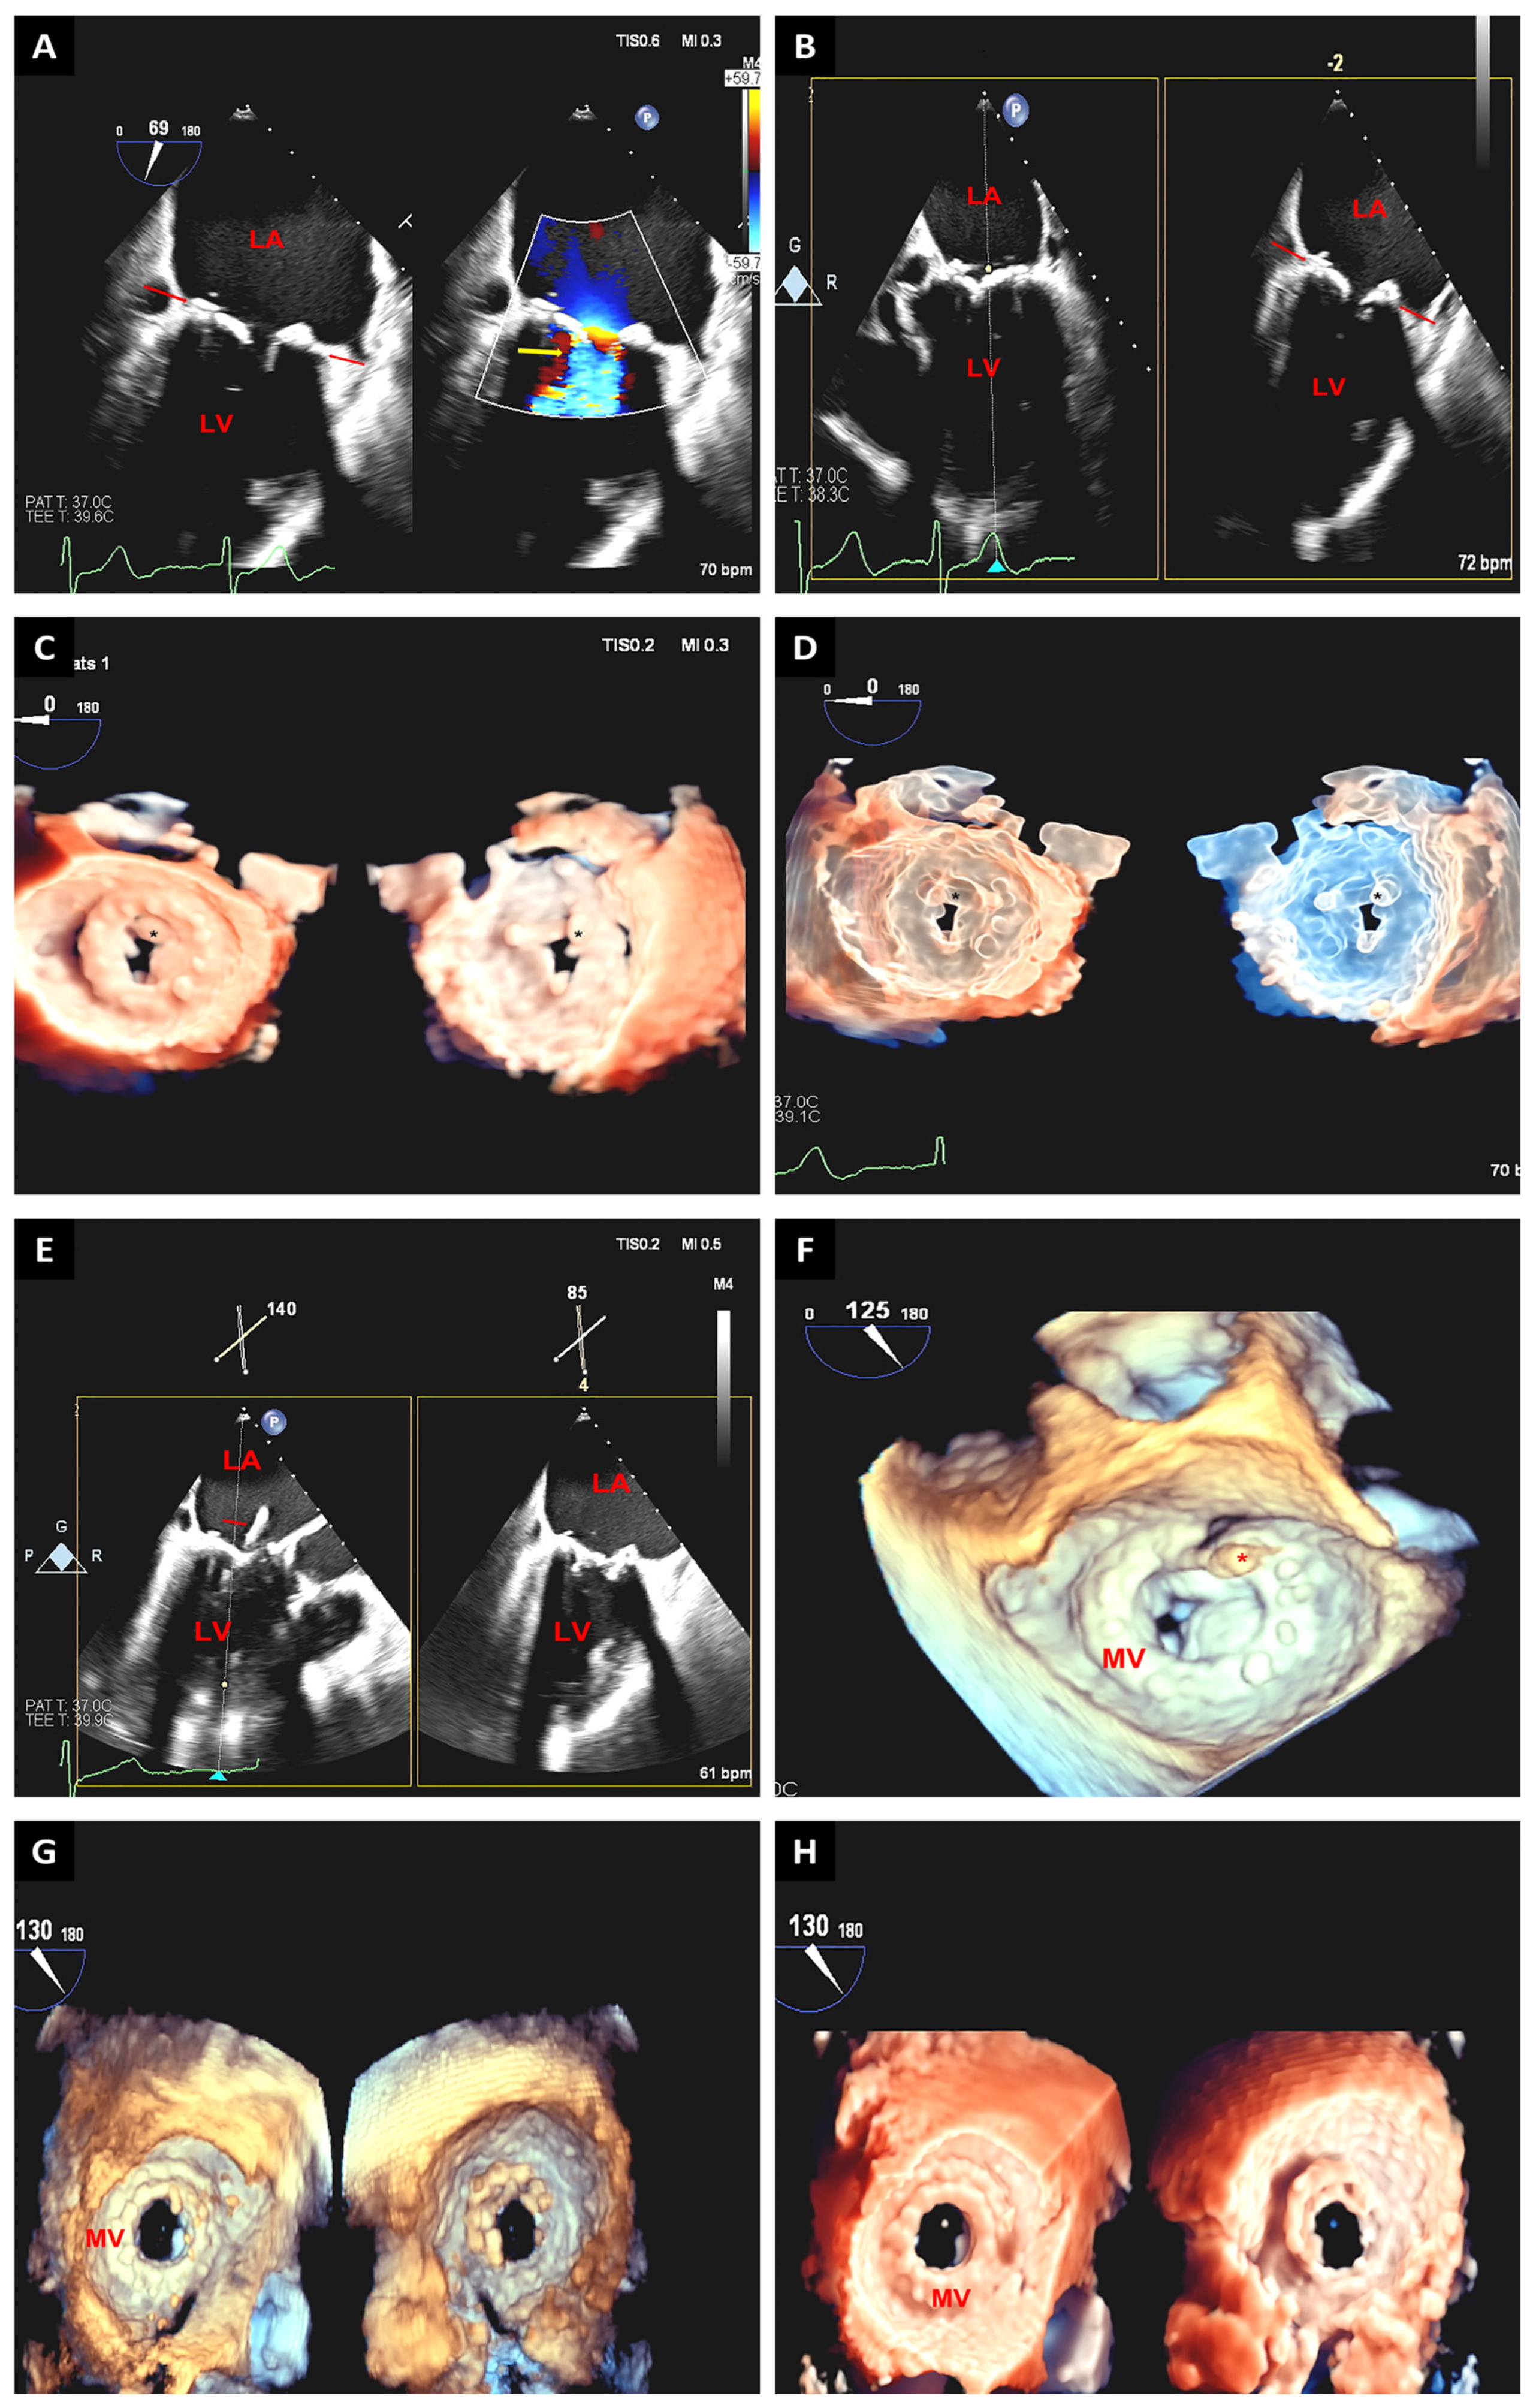

3.2. Mitral Valve Interventions

3.2.1. Edge-to-Edge Mitral Valve Repair

3.2.2. Transcatheter Mitral Valve Replacement